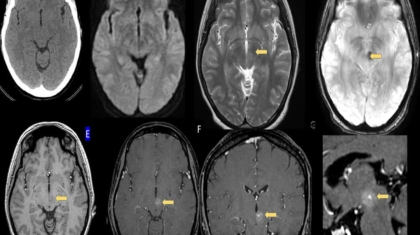

23 year old lady with tingling numbness in the right upper limb

No focal deficits

No significant past history

No neurological deficits on examination

MRI BRAIN (P+C) done for further evaluation